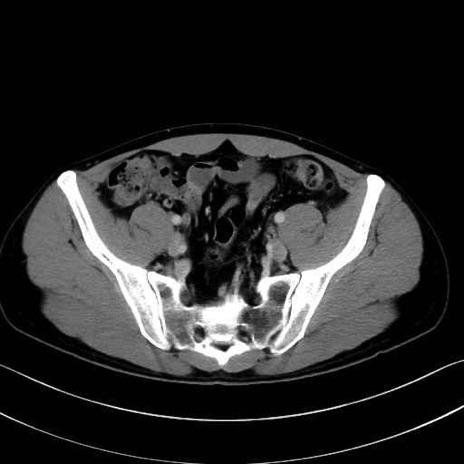

3. 殿部の筋肉(表層・中層・深層)

大殿筋 (Gluteus maximus)

中殿筋 (Gluteus medius)

小殿筋 (Gluteus minimus)

大腿筋膜張筋 (Tensor fasciae latae)